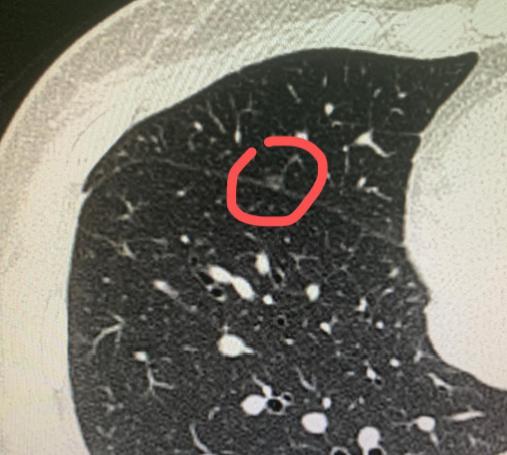

命运有时候很残酷,但还是会留一扇窗!刘先生查出肺癌时已经是晚期了。其实早几年他就常常胸背痛,可一直没太在意,烟也照抽。 直到后来开始咳血,才不得不来医院检查,可惜为时已晚。 陪哥哥住院期间,他妹妹心里总觉得不踏实,也顺便做了一个胸部CT。结果发现右肺有三个磨玻璃结节,最大的一个有9毫米,中间已经有了实性成分。 我告诉她,这种情况需要先观察,三个月后再来复查,如果是炎症,结节有可能会缩小或消失,得给自己和身体一点时间。 三个月后复查,结节还在,大小形态几乎没变,边缘也很清楚。从影像上看,肿瘤的可能性比较大。不过好在三个结节都靠近肺的外周,如果手术,创伤也相对较小。 当时她哥哥病情加重,需要人照顾,加上患者自己也有些顾虑,我们商量后决定再随访观察一段时间。对于含有磨玻璃成分的结节,发展通常比较慢,等半年再来复查也是安全的。 半年后她再次来到门诊,提起哥哥已经去世了,语气里都是遗憾:“要是他能早点发现就好了……” 这次复查,她的结节依然稳定,但肿瘤性质已经比较明确。她这次来,也是下定决心要做手术了。 近日我们为她做了微创手术,术后病理结果显示三个结节都是肺癌,包括原位癌、微浸润癌和浸润癌。一次手术,把三个问题都解决了。 这个病例告诉我们,尤其对于长期吸烟、或有肺癌家族史的人来说,每年的低剂量螺旋CT筛查真的不能忽视。 很多时候,早点发现,结局就会完全不同——早期肺癌是可以通过手术达到治愈的。 健康这件事,多留一份心,或许就多一个机会。[玫瑰][作揖]